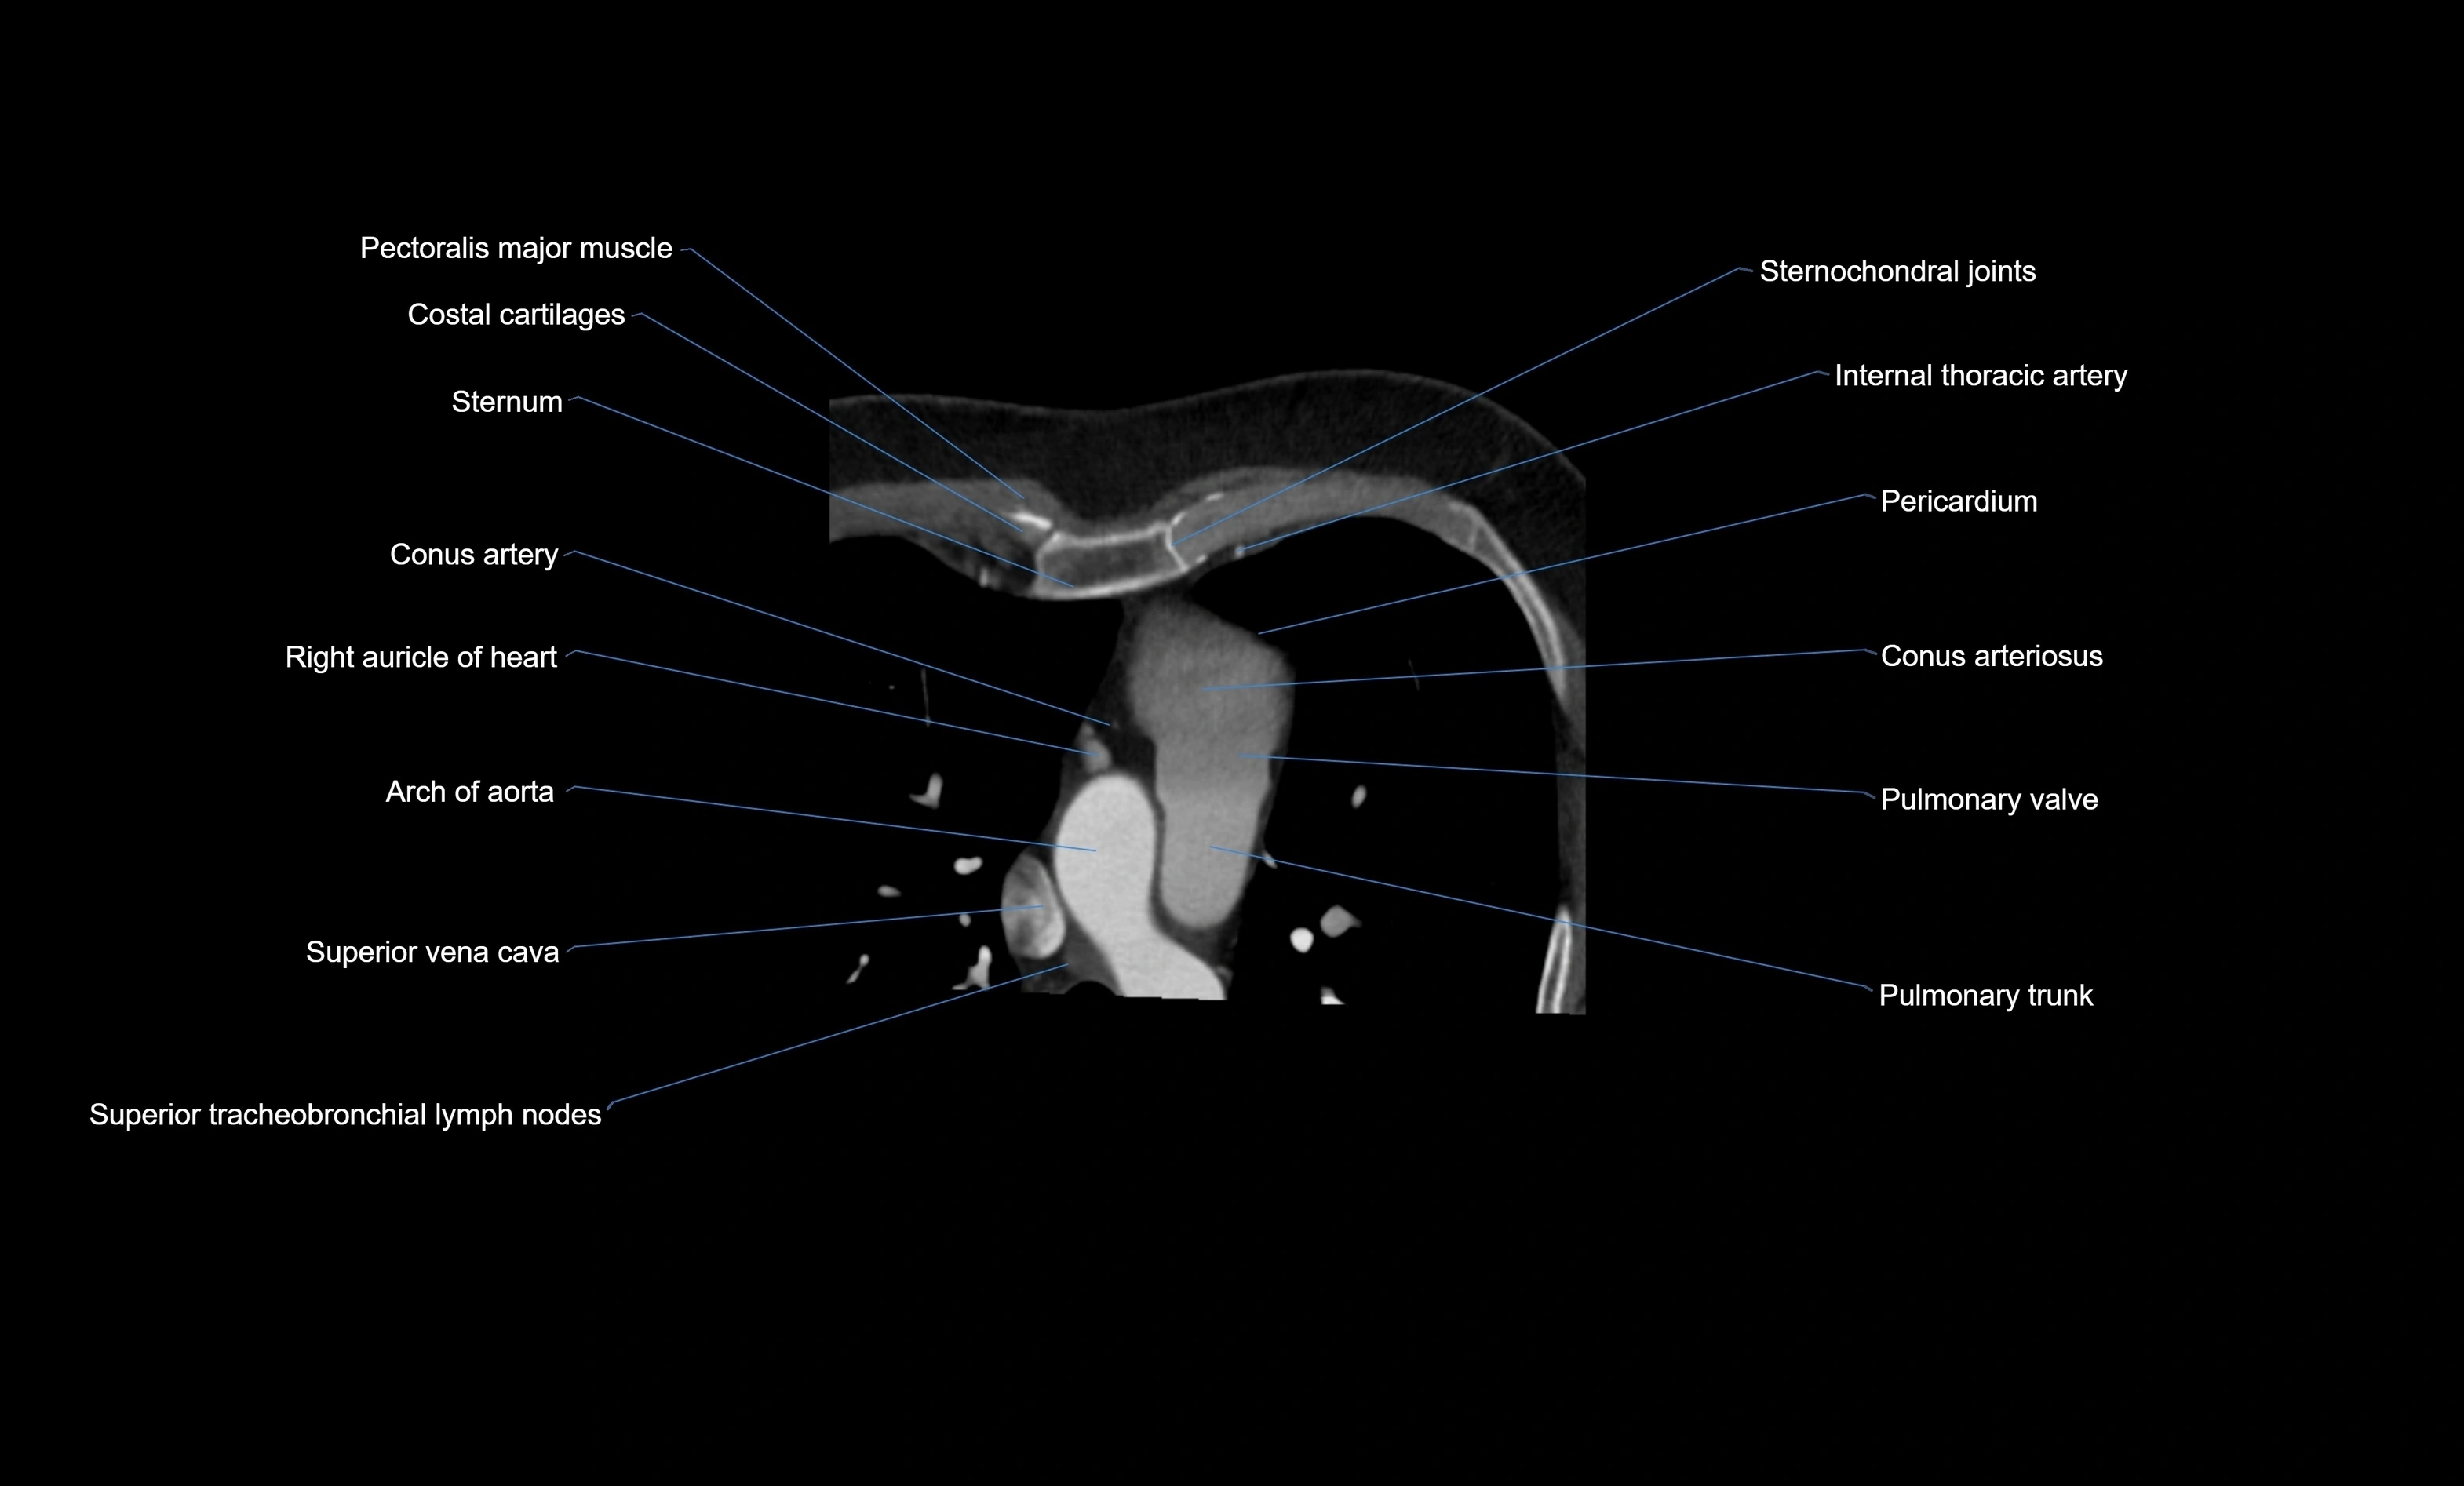

- Arch of aorta

- Body of sternum

- Conus arteriosus

- Conus artery

- Costal cartilages

- Pericardium

- Pulmonary trunk

- Pulmonary valve

- Right auricle of heart

- Sternum

- Superior tracheobronchial lymph nodes

- Superior vena cava